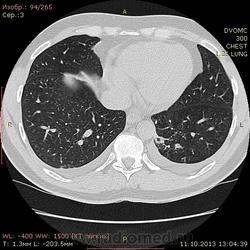

Пациент 35 лет. На УЗИ нашли житкость слева в плевральной полости, отправили на КТ - жидкость с обеих сторон. Из разговора с больным выяснилось, что около 1,5 месяцев назад была высокая тенпература, кашель - никуда не обращался и не лечился. На момент исследования ни на что не жалуется.

Похоже слева в S10? на поствоспалительные изменения? или на что похуже? И если на стороне поражения можно понять окуда жидкость, то справа - можно расценивать как реакция плевры на воспаление слева?

Локальный фиброз субсегмента S10 слева с бронхоэктазами. Двусторонний малый гидроторакс (толщина слоя жидкости до 1 см≈объём до 50 мл). Интересная субкапсульная ерундовина в S6 печени, наверное киста.